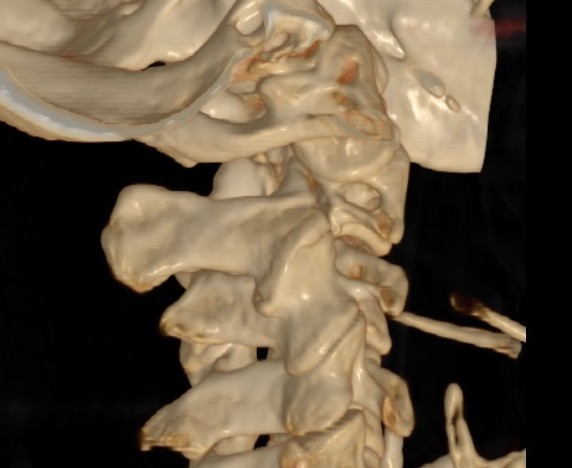

Bilateral pars fracture of C2

Traumatic spondylolisthesis of C2

CT scan